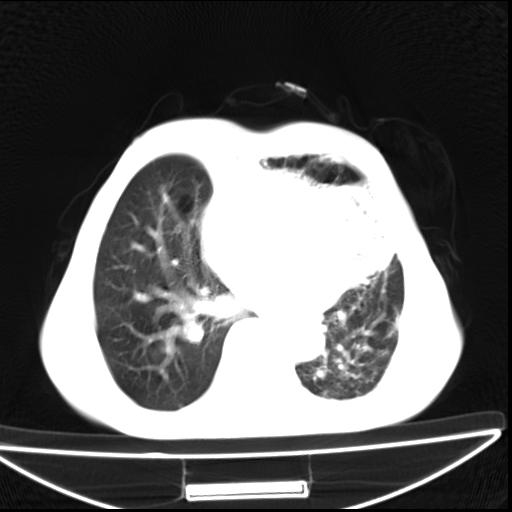

男  70岁,发烧咳嗽4天。盗汗,消瘦。无痰中带血丝,以前有肺tb病史,ct见,双肺tb,左侧胸廓塌陷,左胸膜肥厚粘连。纵隔移位,右侧胸腔积液,大家说说那个心影前左肺舌叶除了肺大炮还有炎症还是干酪性肺炎?有占位吗?我看纵隔淋巴结也大。

1)两肺继发性肺结核并左肺上叶肺不张,支气管扩张。2)双侧胸膜炎(胸膜增厚+少量胸腔积液)。

双肺继发性肺结核伴部分左肺毁损!

双肺继发性肺结核伴部分左肺毁损。